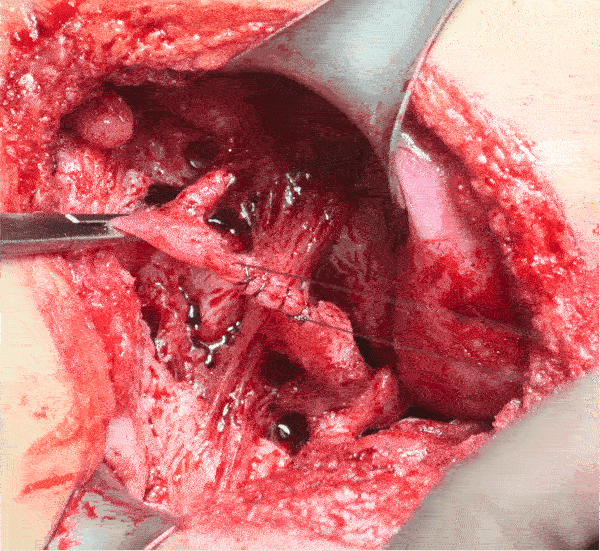

앞에서 승압제를 써서 문제가 됐던 극 중 장면에서 환자 복부 수술부위에 피가 차오르는 장면이 나옵니다. 그것을 보고 나서야 백강혁 선생이 승압제때문에 수술부위에서의 출혈량이 늘었다고 마취과 (=밤톨)를 비난하는데, 극에서 보여주는 출혈양과 속도는 단순히 혈압이 높아져서 늘어난 출혈정도를 훨씬 넘어섭니다..

수술부위에서 그 정도 속도로 차오르려면 최소 정맥이나 작은 동맥의 출혈이 있다고 해야만 설명이 가능한 출혈속도입니다. 혈관을 수술 실로 타이를 한 직후에 그 정도 속도의 출혈이 있다면, 당연히 타이가 제대로 되었나부터 의심을 하는 것이 보다 순리가 아닐까 합니다.

물론 드라마상 시각적으로 출혈을 보여주기 위한 과장된 연출일 수도 있습니다만, 승압제 썼다고 덮어놓고 마취의를 비난하기에는 너무 성급했다고 보는 것이 맞는 것 같습니다.

Surg_Field_08.gif 수술부위의 출혈속도가 단순 혈압 상승이 원인이라기엔 너무 빠르다.

승압제를 써서 혈압을 올렸기 때문에, 환자 수술부위의 출혈이 증가했다고 하는 것은 외과의사들의 흔한 착각 혹은 마취과를 비난하기 위한 핑계일 뿐입니다.